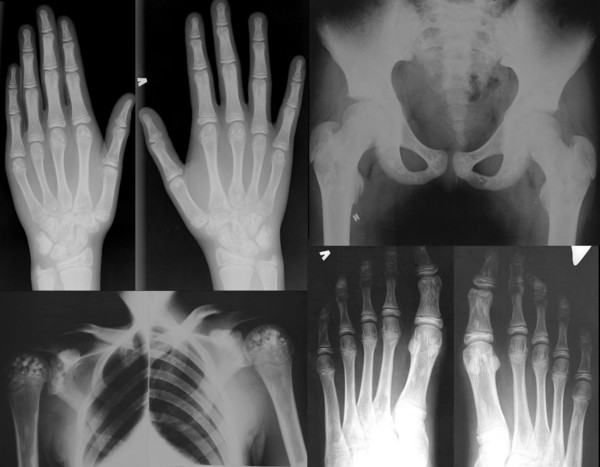

La meloreostosi è una patologia dello sviluppo e una displasia mesenchimale in cui la corticale ossea si allarga e diventa iperdensa in una distribuzione sclerotomica. La condizione inizia durante l'infanzia ed è caratterizzata da un ispessimento delle ossa. Il dolore è un sintomo frequente e spesso l'osso può assumere un aspetto di una cera di candela che gocciola.